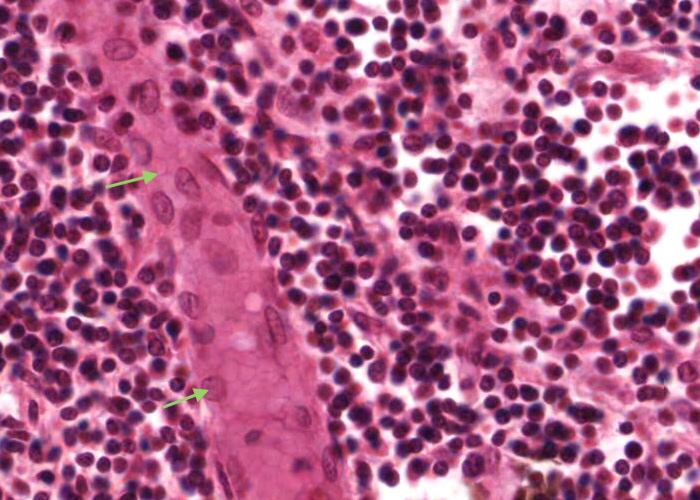

The important specializations of this vasculature are the tall postcapillary venules (TPCV), also called high endothelial venules (HEV). These vessels are lined by specialized cuboidal epithelium, look for an oval shaped nucleus (sometimes even described as columnar) instead of the usual squamous variety. They are located in the paracortex as the first segments of the venules.

Recall their role in the pathway of lymphocyte circulation. See if you can find several examples and even some sectioned transversely (see next item). If not, you will have no problem recognizing them if you go back and re-examine the section of the tonsil.

In this image, the tall postcapillary venule (TPCV), also called a high endothelial venule (HEV), is sectioned transversely. Look for an oval shaped nucleus (sometimes even described as columnar) instead of the usual squamous variety.

Some lymphocytes live for a very long time and so recirculate continuously. Their "homing behaviour" is a consequence of molecules on their cell surface interacting with complementary molecules on the endothelial cell surface of these specialised venules.